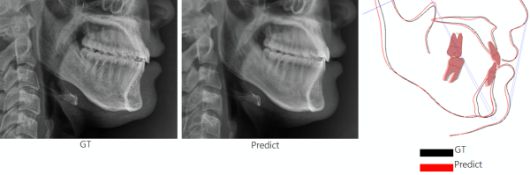

해당 AI 모델 정확도를 검증한 결과 연구에 참여한 교정 전문의와 구강악안면외과 전문의들은 AI가 생성한 예측 영상과 실제 수술 후 촬영한 영상을 구분하지 못했으며, 두 영상에 표시된 해부학적 기준점(계측점) 간 평균 오차는 대부분 1.5mm 이하일 정도로 매우 높은 정확도를 보인 것으로 나타났다.

특히 AI 모델의 예측 정확도를 검증하기 위해 교정 전문의 2명과 구강악안면외과 전문의 2명이 AI가 생성한 영상과 실제 수술 후 촬영된 영상을 구별할 수 있는지 확인했다. 이 결과 전문의 둘 중 AI가 생성한 영상을 구분해 낸 비율은 48%를 기록해 두 영상을 거의 구분하지 못한 것으로 나타났다.

이와 함께 AI가 예측한 영상과 실제 수술 후 영상의 계측점 간 평균 오차는 대부분 1.5mm 이하였다. 이는 같은 대상을 두 번 측정할 때 발생하는 오차와 유사한 수준으로 의료 현장에서 활용될 수 있을 만큼의 정밀도를 확보한 것으로 평가된다.